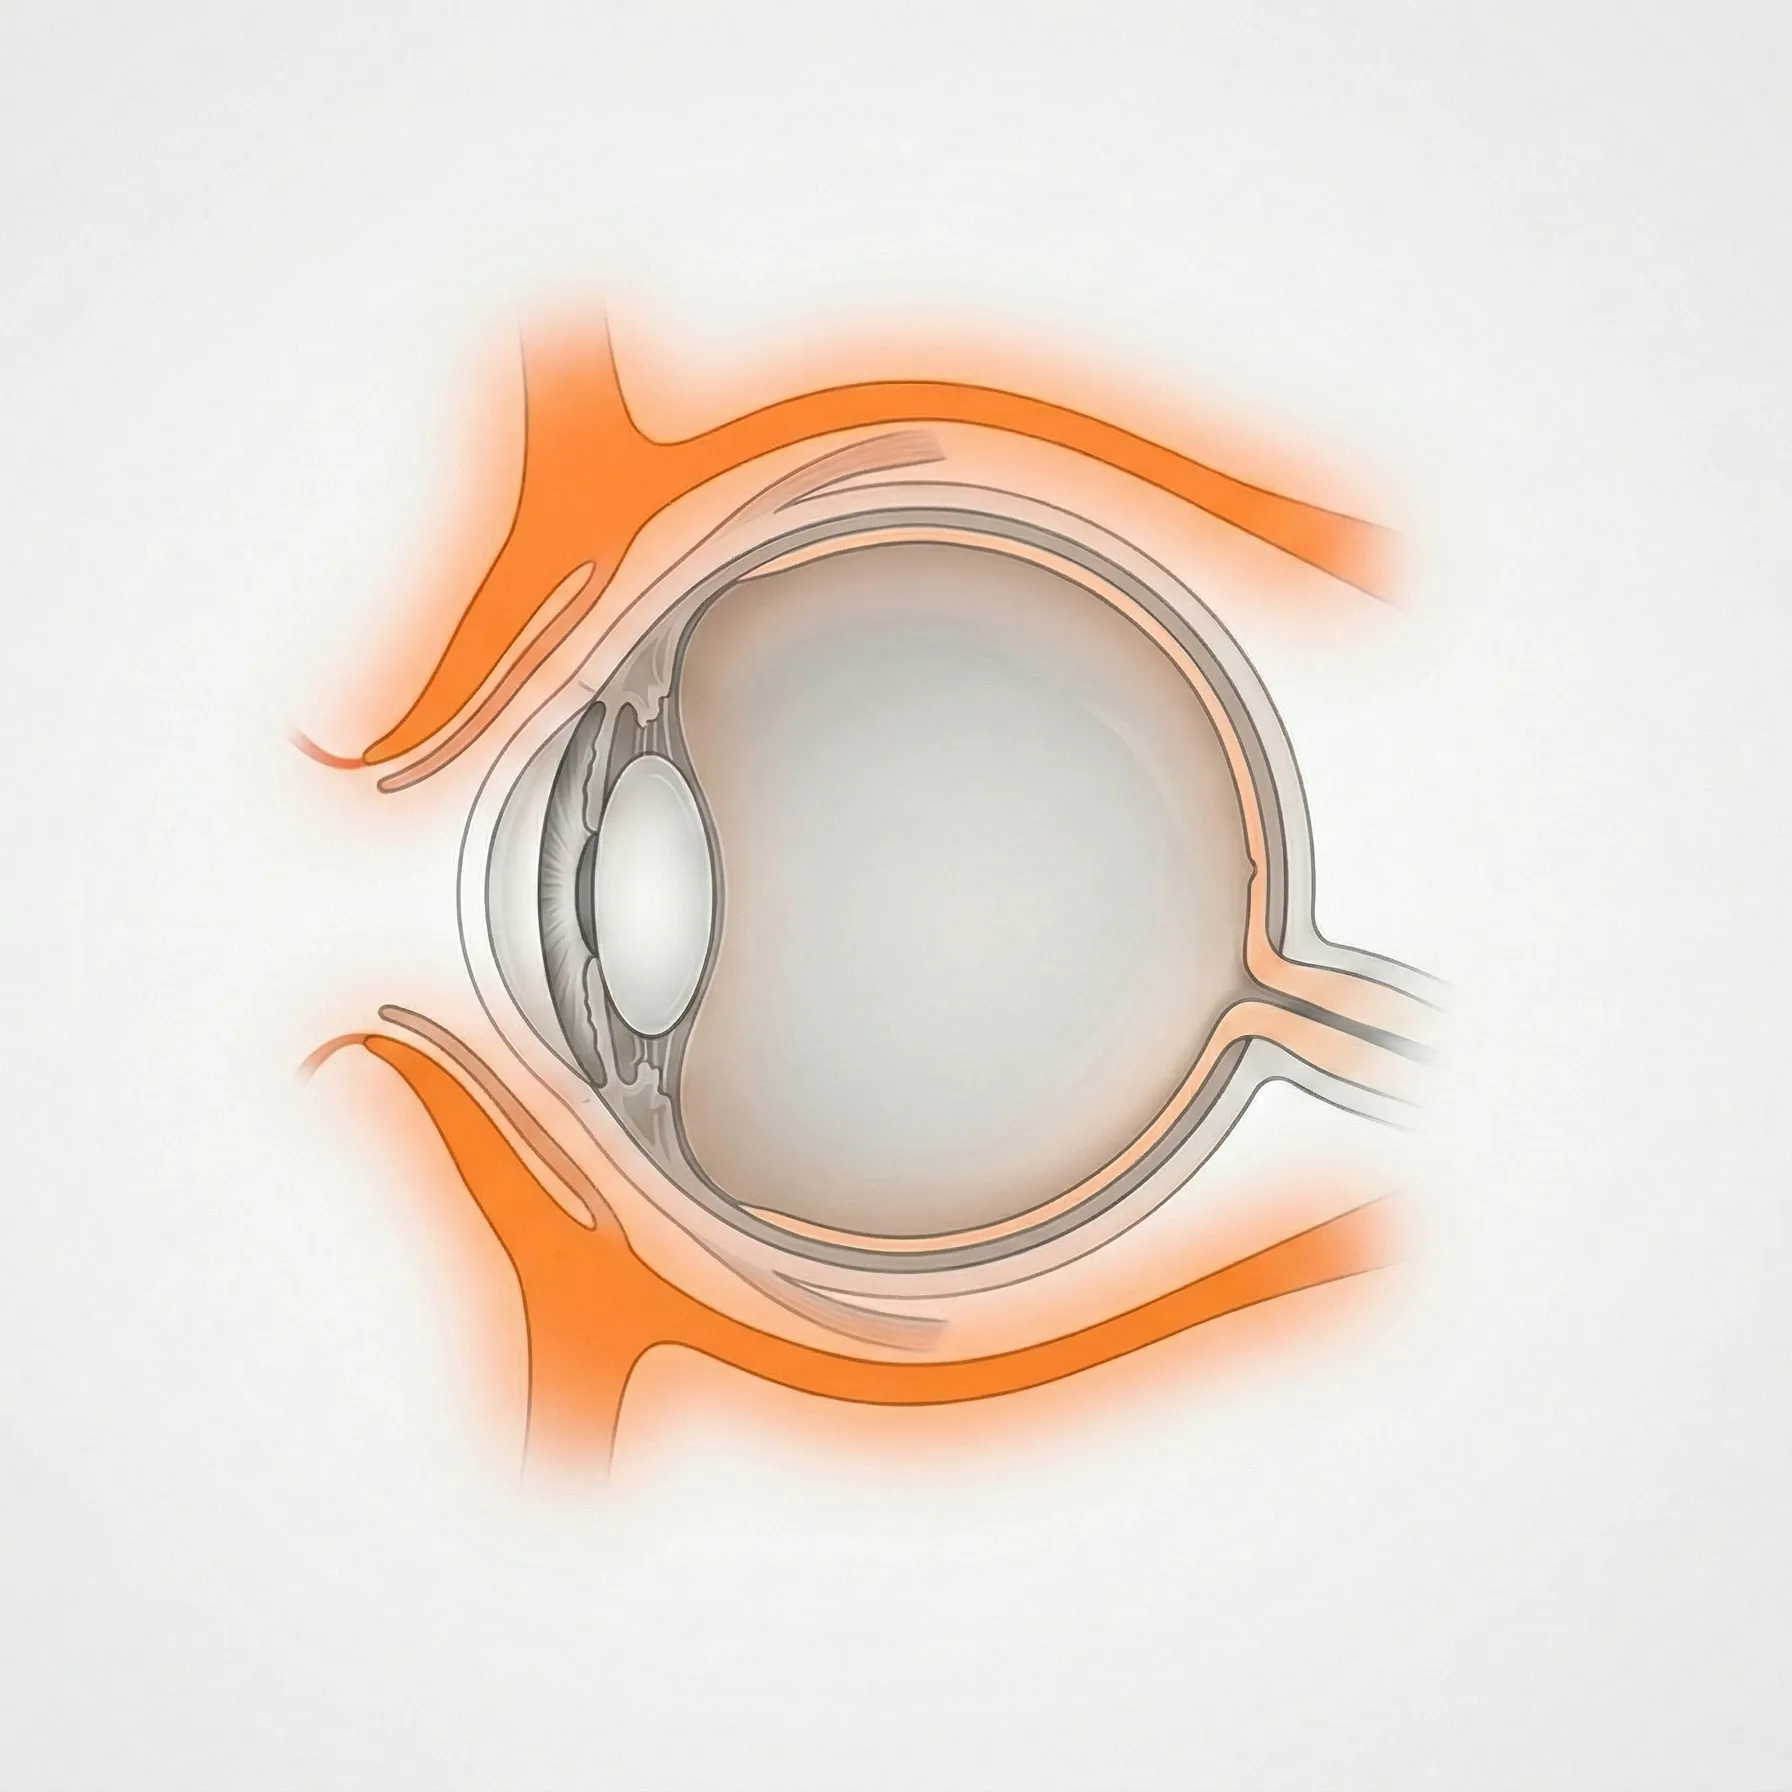

眼球の周囲には、まぶた(眼瞼)・涙の通り道(涙道)・眼球が収まる骨のくぼみ(眼窩)など、眼の機能を支えるさまざまな付属器があります。このカテゴリでは、これらの組織に生じる形態異常・機能障害・炎症性疾患を扱います。